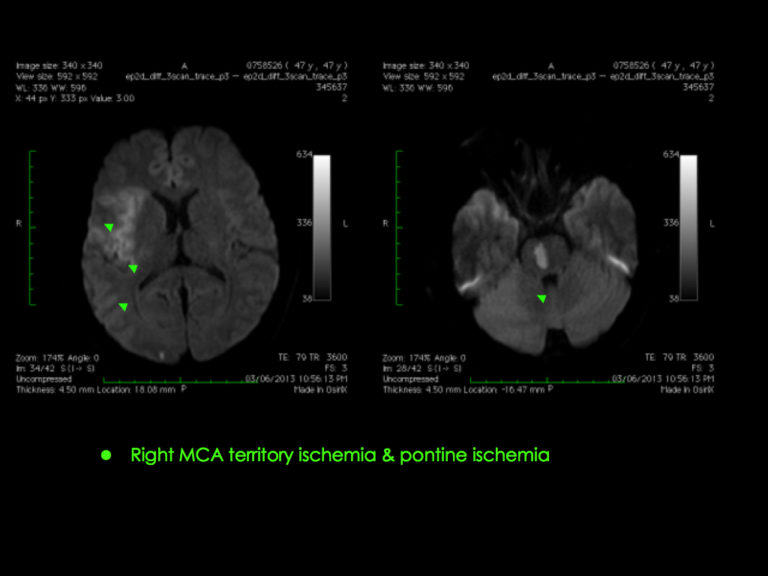

As many as 7 out of 10 stroke patients in Hong Kong have the blockage of the ischaemic type. Although it is less severe than a haemorrhagic one, it calls for immediate treatment to prevent the condition from worsening. That is why we, at the HKBSSP emergency stroke care clinic, are available round-the-clock to help patients in need.

It’s of paramount importance to resist the ischaemic attack within the first 8 hours to put brain damage to a bare minimum. This way, we can ramp up your chances of living a healthy and happy life thereafter.